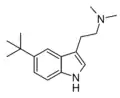

| 5-(t-Butyl)-DMT [11] | artificial | 5-C(CH3)3 | CH3 | CH3 | 5-(tert-butyl)-N,N-dimethyltryptamine | |